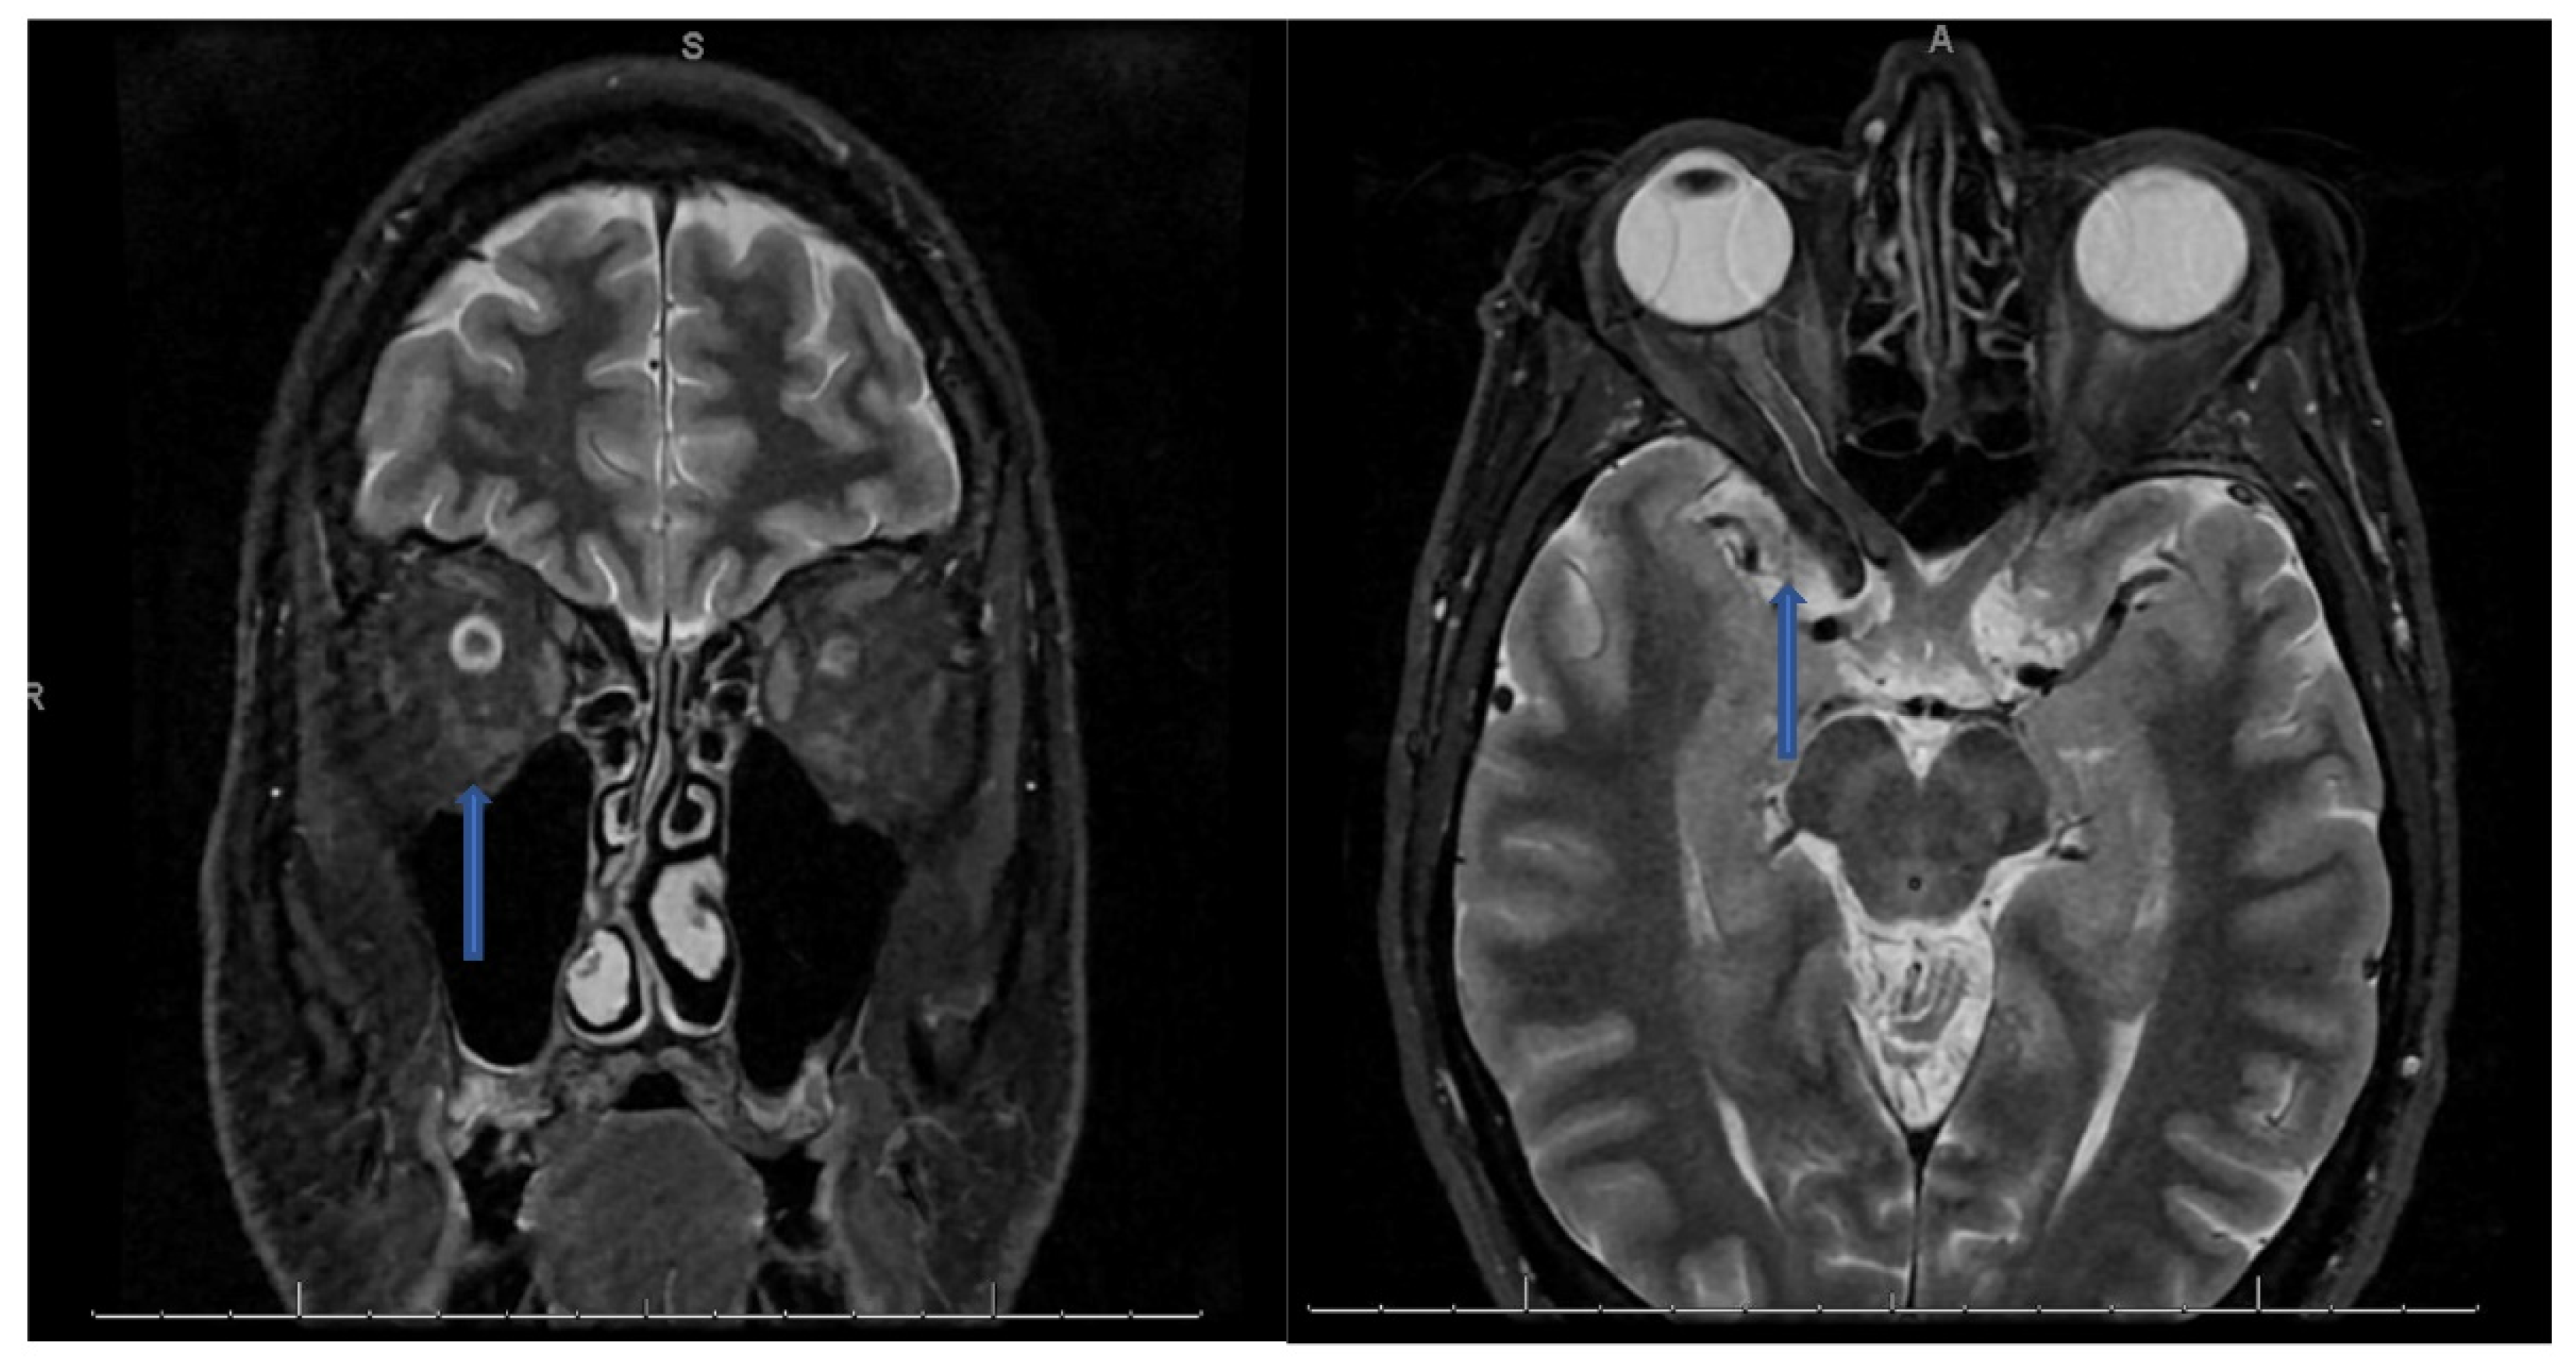

CSF analysis showed lymphocytic pleocytosis with hypo-glycorrhachia and elevated protein suggesting an inflammatory or infectious process (see table below). CSF cultures and meningitis/encephalitis panel were also negative. NMO/MOG/AQP4 antibodies negative. Myelin Basic Protein was found to be elevated at 24.5 ng/ml (Ref interval 0.00–5.50 ng/mL). Oligoclonal bands were also found to be positive with 9 bands detected and IgG Index elevated at 1.81 (Ref Interval: 0.28-0.66). MRI of the orbits with contrast revealed bilateral optic neuritis/perineuritis, with features suggestive of an inflammatory and/or infectious process (Figure 1). MRI brain with contrast was unremarkable for intracranial lesions.

Figure 1. Coronal T2 STIR sequence (left) showing hyperintense signal prominently within the right optic nerve than the left with an axial T2 sequence (right) showing hyperintense signal along a segment of the right optic nerve.